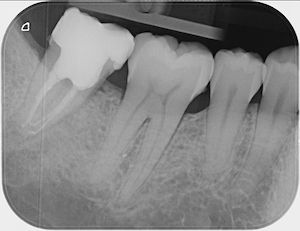

19.1.26: Der -7 wurde beim Pressen stark belastet und hat stark geschmerzt.

Beide apikalen Aufhellungen sind sehr klein.

Ist die Ursache bakteriell oder nur mechanisch?

Die Patientin spürt, dass sie häufig ihre Zähne zusammenpresst. Deswegen hatte sie am 19.1.26

starke Schmerzen links unten.

Am 22.1.26 waren diese verschwunden, dafür schmerzte nachher die Wange links oben.

Bei den oberen Molaren zeigt das Röntgenbild keine Aufhellung.

Ist der -7 entzündet und braucht er eine Wurzelbehandlung?

Stattdessen hab ich ihr eine FOS-Knirscherschiene gemacht. Diese wird zeigen, ob die Beschwerden wieder aufhören.

Die Patientin hat einen Nachtbruxismus und spürt morgens verspannte Wangen. Sie hat nur Kontakt auf den hintersten Molaren und keine Schmerzen. Das reibende Geräusch ist wahrscheinlich eine stabile Diskus-Degeneration und braucht keine Behandlung.